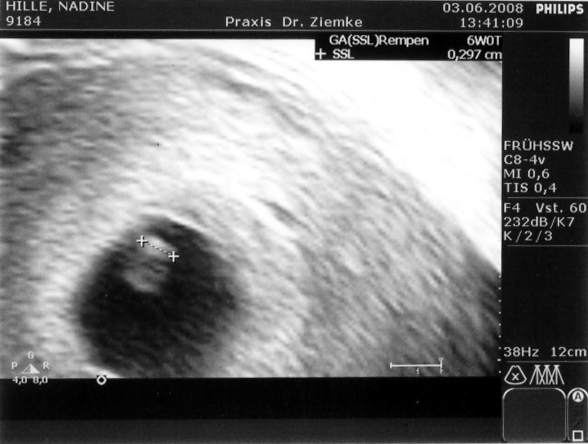

3 Millimeter Kind – das ist die Ausbeute des heutigen Arztbesuches. Und das Herz flattert auch schon. Was man also bis jetzt erkennen kann, ist alles in Ordnung – trotz der Hochzeit vergangene Woche.

Das kleine Teil wird wohl so etwa sechs Wochen alt sein. In drei Wochen wissen wir mehr, wenn Nadin ihren nächsten Termin hat. Voraussichtlicher Geburtsttermin ist dann aber wohl irgendwann zwischen Mitte Januar und Anfang Februar – sagt der Papa mal, der ja gut in Mathe ist ;)